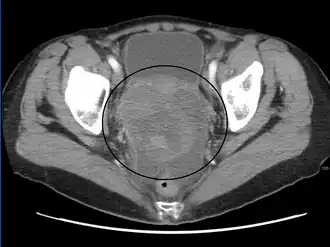

The preliminary diagnosis begins with a pelvic examination, serum tumor marker test and imaging. Physicians may feel a large palpable mass or lump in lower abdomen upon insertion of the gloved fingers into the vagina. To further identify the histologic subtypes of OGMTs, blood samples of patients are collected to analyse the serum level of biomarkers released by the tumor cells. A surge in the plasma levels of human chorionic gonadotropin and alpha-fetoprotein is indicative of OGMTs.[1] Lactate dehydrogenase, alkaline phosphatase and cancer antigen 125 might potentially increase as well.[19] To visualize the location and morphology of the tumor, transvaginal ultrasonography is usually employed.[1] The most characteristic appearance is a parenchymal-like heteroechoic mass with sharp borders and high vascularization.[1] Computed tomography would produce stacked image inside the peritoneal region of the body to visualise the lobular pattern of the tumour.[1] Usually for dysgerminoma, solid mass being compartmentalized into lobules with enhancing septa may be evident for haemorrhage or necrosis.[1]